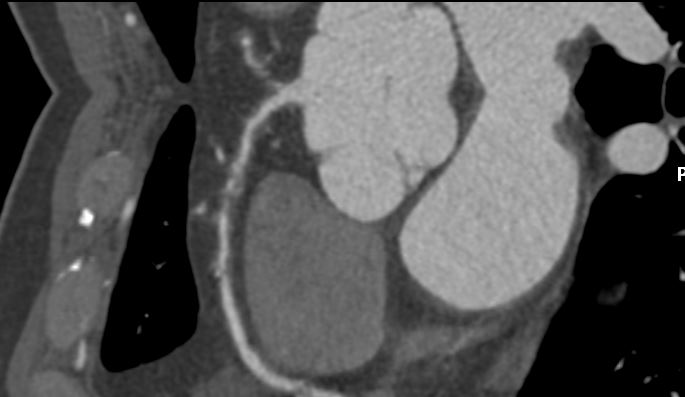

Echocardiogram showed good left ventricular ejection fraction of 53%. A multislice computed tomography coronary angiogram (MSCT-Coronary) demonstrated severe stenosis involving the proximal left anterior descending (LAD),proximal left circumflex (LCx),and proximal right coronary artery(RCA).The patient was subsequently admitted electively for diagnostic coronary angiography and possible percutaneous coronary intervention (PCI).

Angiographic assessment showed a normal left main stem, with severe proximal LAD disease exhibiting moderate calcification and providing retrograde collateral supply to both RCA and LCx. The LCx demonstrated severe mid-segment disease with subtotal occlusion of the obtuse marginal 1 (OM1) branch. The RCA showed severe proximal disease and total occlusion of the posterolateral(PL) branch.